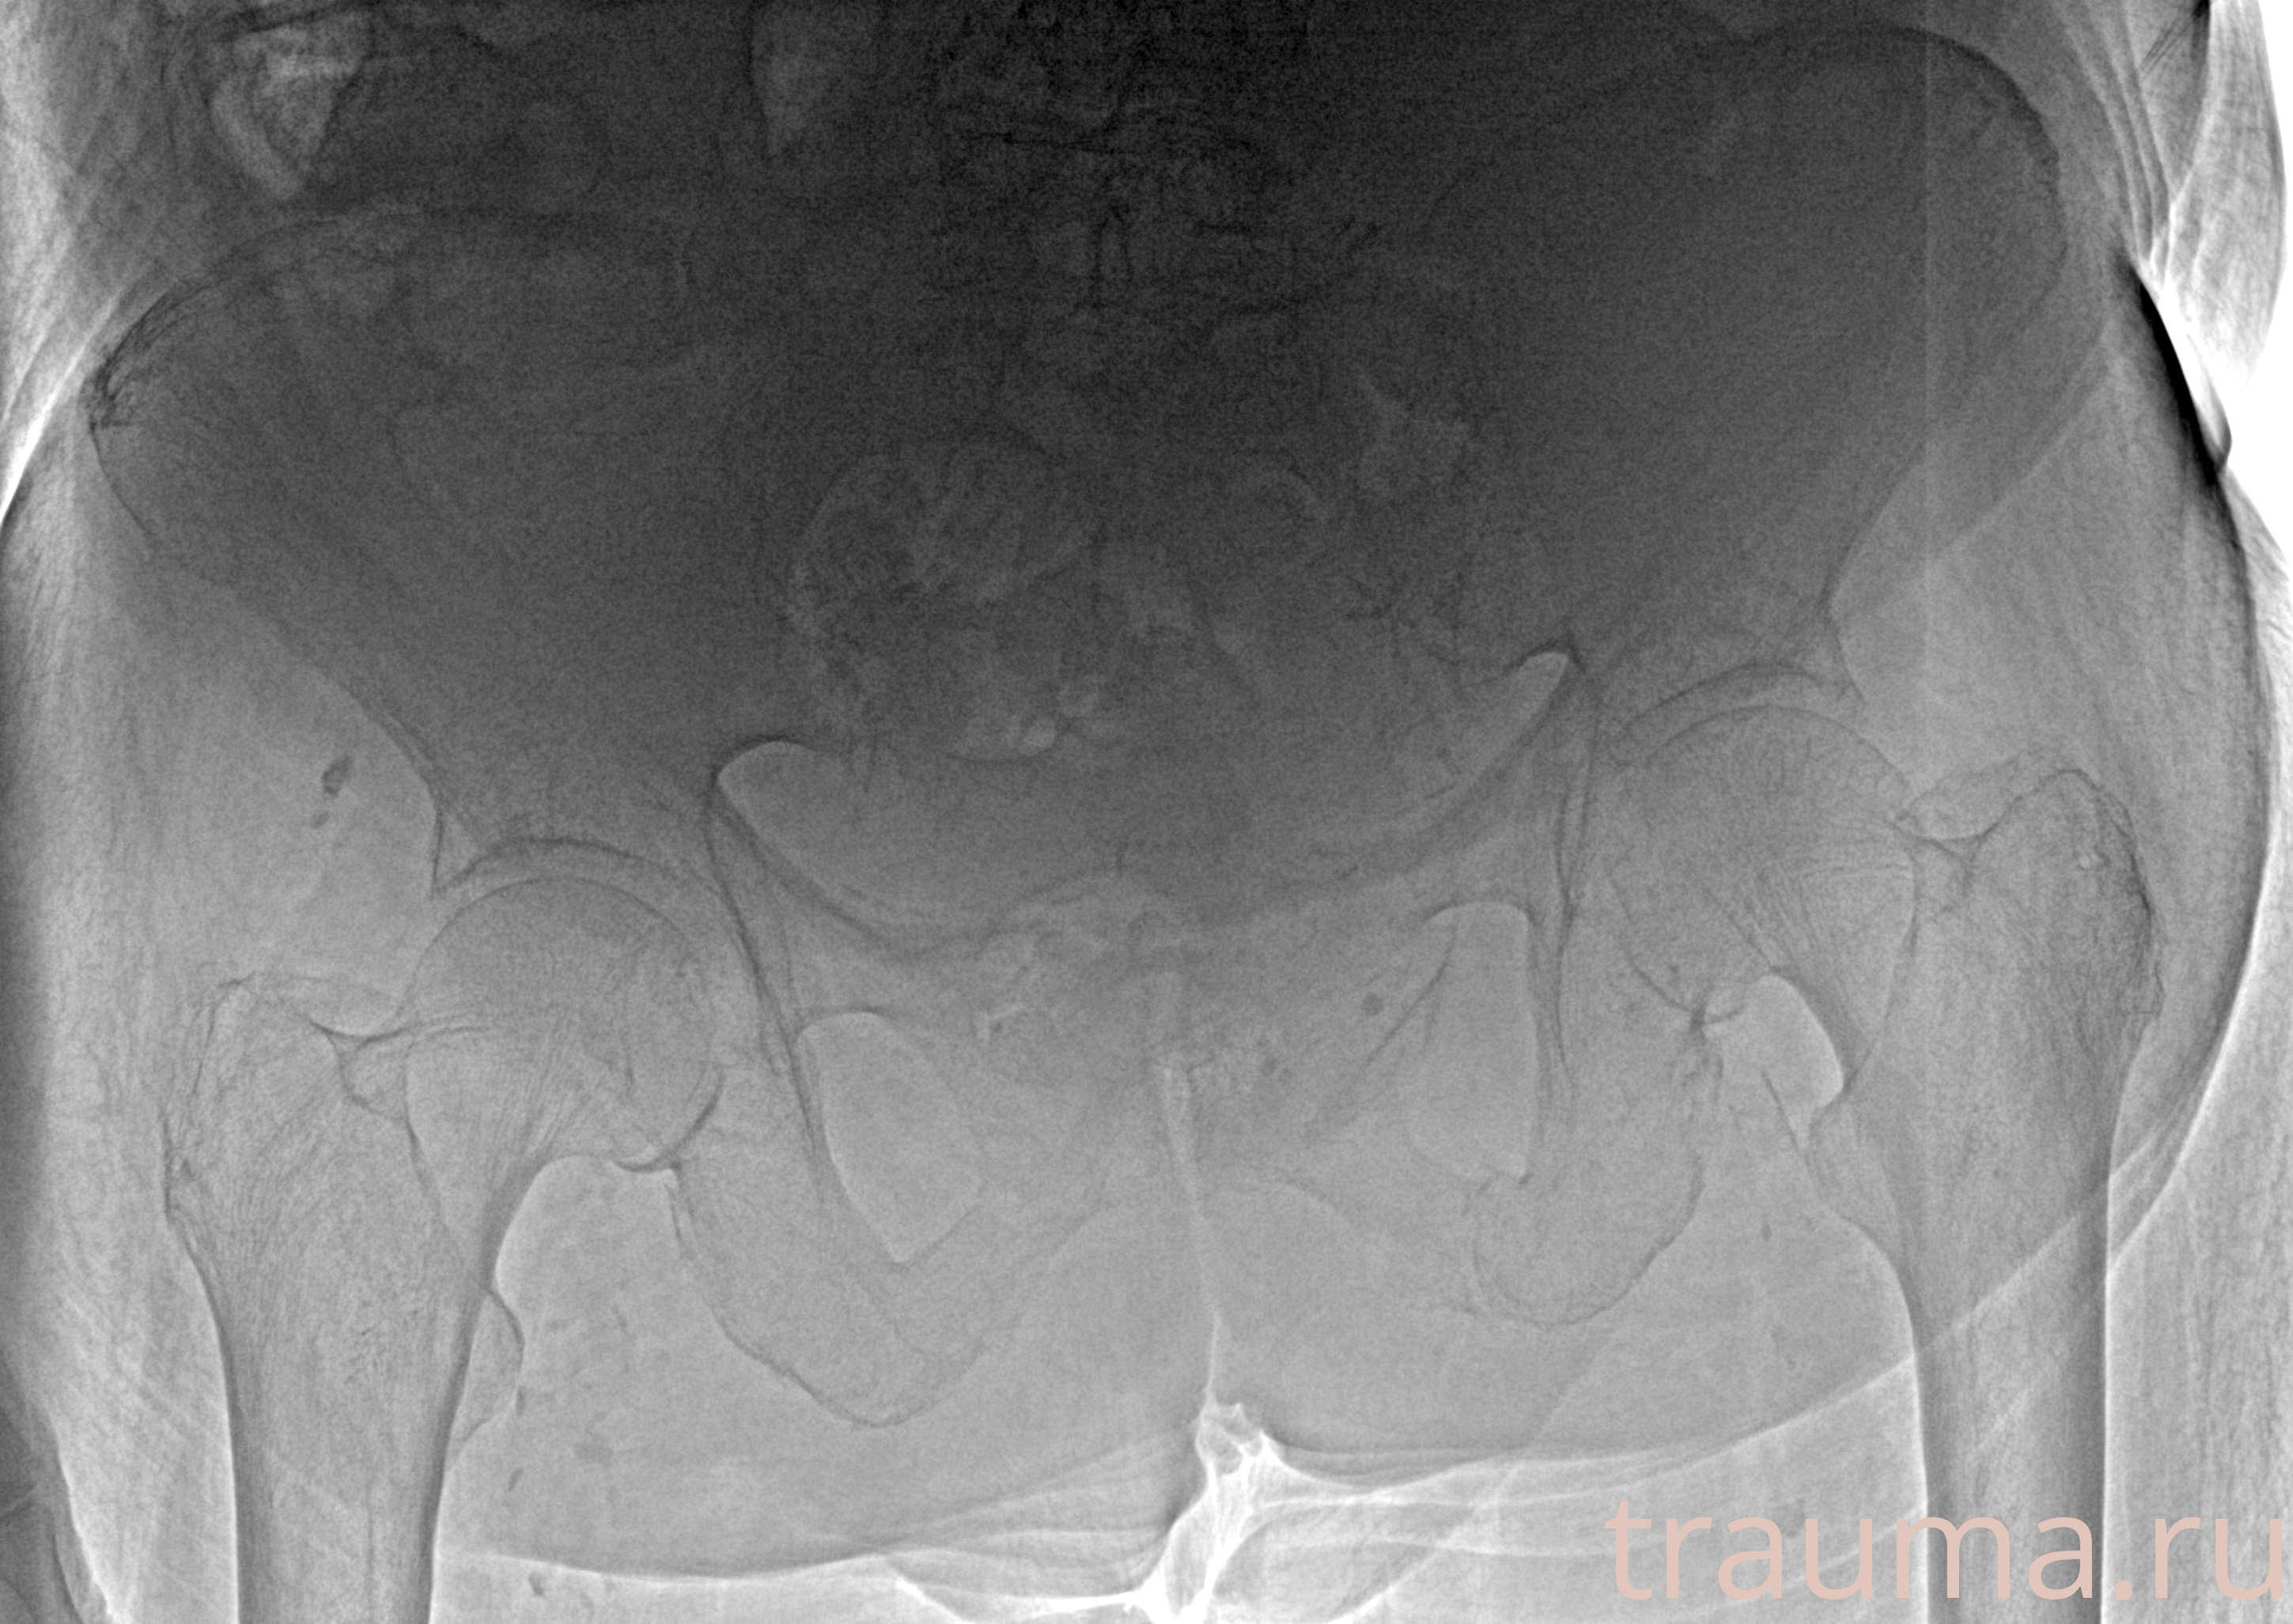

Рентгенограммы

Рентген на дому: по вашему адресу приезжает врач-рентгенолог, травматолог-ортопед с мобильным рентгеновским аппаратом, проводит диагностику травмы или заболевания, делает необходимые рентгенограммы, дает рекомендации по дальнейшему лечению. Получить качественные снимки в домашних условиях возможно благодаря уникальной методике, разработанной МосРентген Центром для института  Склифосовского